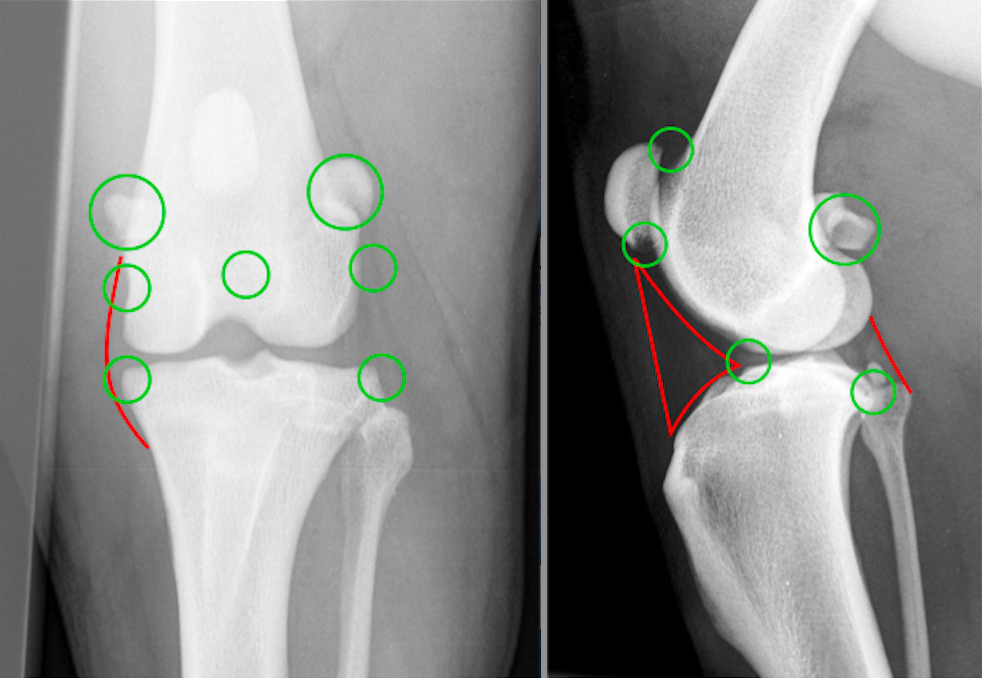

Røntgen! - Lav 2 ortogonale billeder - Evt oblique og stress også

Hvordan ser korsbånd ud på røntgenbilleder?

De er soft tissue = ikke på røntgen

Hvor ses hhv degenerative ændringer og hævelser oftest?

Grønne cirkler: degenerative ændringer

Røde streger: hævelser

Hvorfor har hunde brug for korsbånd?

Stabiliserer tibia-femur.

Patellaligamentet er ikke helt lodret, og trækker derfor lidt frem i tibia.

Denne bevægelse stopper CL.